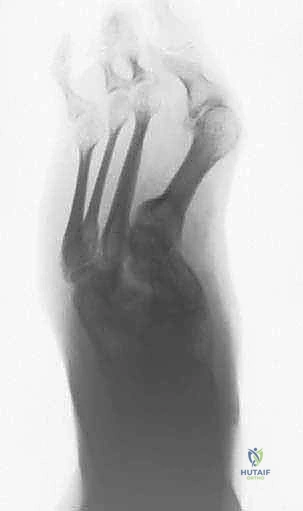

تشوهات أصابع القدم الصغيرة: دليل شامل للعلاج الجراحي وغير الجراحي مع الأستاذ الدكتور محمد هطيف في صنعاء

هل تعاني من آلام وتشوهات أصابع القدم الصغيرة؟ يقدم الأستاذ الدكتور محمد هطيف في صنعاء أحدث طرق التشخيص والعلاج الجراحي وغير الجراحي لتصحيح …